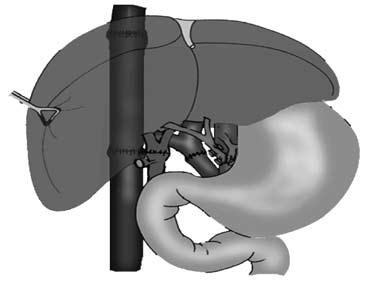

Все эти методы лечения, к сожалению, паллиативные и направлены на устранение ведущего осложнения заболевания – кровотечения из варикозных вен пищевода. Поскольку это лечение симптоматическое, то заболевание постепенно прогрессирует и заканчивается печеночной недостаточностью и смертью больного. Единственным методом радикального лечения заболевания является пересадка печени (рис. 91). В настоящее время разработаны несколько вариантов этой сложной операции и достигнуты положительные результаты. Хирургическая часть данной проблемы, можно сказать, решена.

Рис. 91. Принципиальная схема ортотопической трансплантации печени